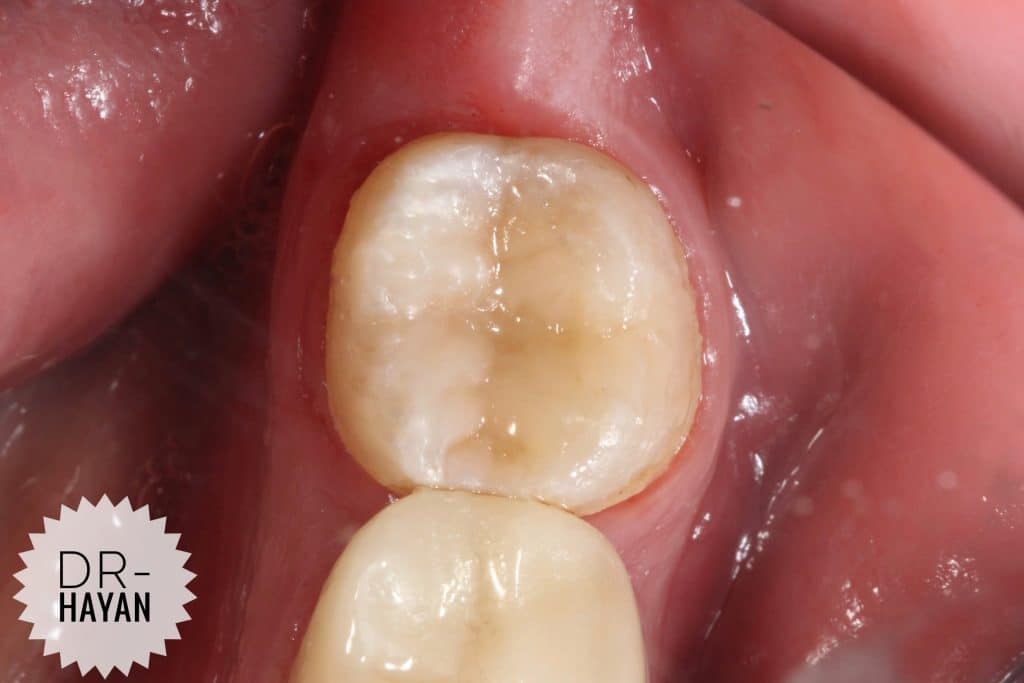

Initial view

lower 8 with Bad anatomy restoration & broken margin

With Sensitivity due to exposed dentin